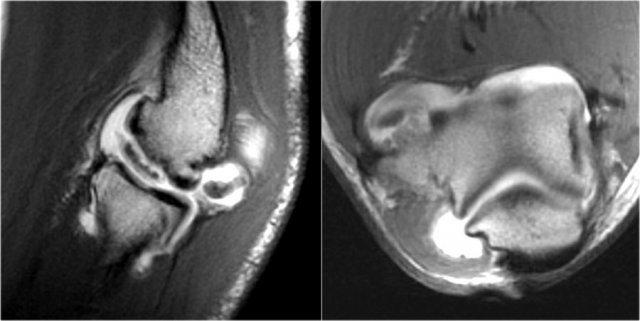

OC lesion of trochlea

Những hình ảnh này của một bệnh nhân bị đau khuỷu tay phía trước.

Không có chấn thương gần đây.

Chẩn đoán lâm sàng là viêm gân cơ nhị đầu hoặc viêm túi hoạt dịch vùng nhị đầu.

Các phát hiện trên hình ảnh MRI mặt phẳng vành khá bất thường.

Nếu bạn thấy điều này ở chỏm con, bạn sẽ gọi đó là tổn thương sụn xương chỏm con.

Đây được gọi là tổn thương sụn xương của ròng rọc.

Lưu ý các thay đổi dạng nang nhỏ (mũi tên trắng).

There is also a small cartilage defect.

Tổn thương xương sụn của ròng rọc thường gặp ở bệnh nhân trẻ tuổi, có bộ xương chưa trưởng thành.

Tổn thương xuất hiện ở ròng rọc bên như trong trường hợp này do tình trạng duỗi quá mức lặp đi lặp lại trong vùng có nguồn cung cấp máu kém.

Nó cũng được thấy ở ròng rọc trong do lỏng lẻo và va chạm sau trong.

Đây là một bệnh nhân khác.

Lưu ý rằng đây là bệnh nhân trẻ tuổi, vì sụn tăng trưởng vẫn còn mở.

Có một tổn thương xương sụn lớn ở ròng rọc xương đùi bên ngoài (mũi tên vàng).

Lưu ý phù nề ở xương dưới sụn (mũi tên đỏ).

Sụn khớp vẫn còn nguyên vẹn.